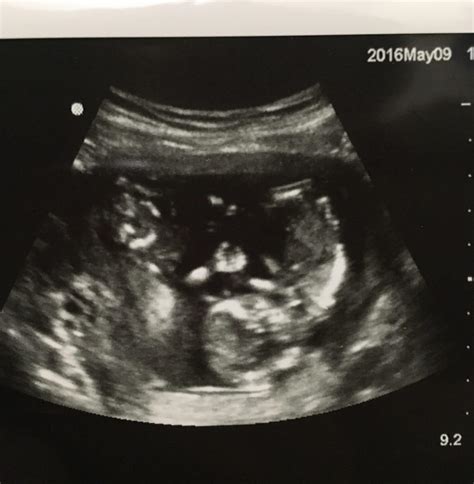

The Ultrasound 16 Week scan, also known as the anatomy scan, is typically performed between 18 and 22 weeks of pregnancy. However, many healthcare providers schedule it around the 16-week mark to ensure that the baby's development is on track. This ultrasound is more detailed than earlier scans and focuses on assessing the baby's anatomy and overall health.

The Ultrasound 16 Week scan is usually performed transabdominally, meaning the ultrasound probe is moved over the abdomen. Here’s what you can expect during the procedure:

• Gel Application: A conductive gel is applied to the abdomen to enhance the transmission of ultrasound waves.

• Probe Movement: The healthcare provider will move the ultrasound probe over the abdomen to capture images from different angles.

• Image Capture: The ultrasound machine will display images on a screen, allowing the provider to assess the baby's anatomy in detail.

• Duration: The scan typically takes about 20-30 minutes, but it can vary depending on the baby's position and the need for additional images.